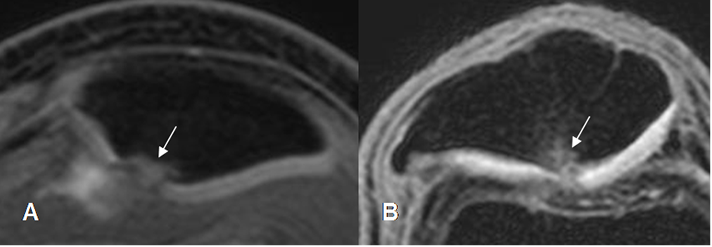

Fig 173. Lesión subcondral.

A: RM 3D axial en T1 STIR y B: RM sagital en STIR. Adelgazamiento del cartílago articular a nivel del vértice, (Flechas delgadas) menor del 50%, con áreas hiperintensas en la patela, que corresponden a lesiones subcondrales. (Flechas gruesas).

Fig 174. Edema óseo.

A: RM 3D T1 STIR. Condromalacia grado 4, con edema óseo reactivo severo, a nivel del vértice.